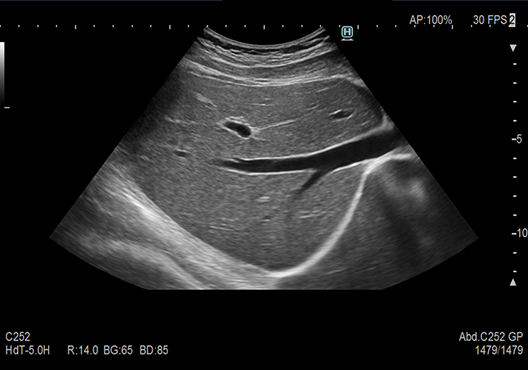

Micro convex transducer (Single crystal) delivering high image quality and easy application in routine examinations. The transducer shape, as well as the performance of the piezoelectric element and heat dissipation structure, have been optimized to achieve both image quality equivalent to a conventional convex transducer, and low-stress operability. In addition, it seamlessly supports examinations in various scenes from diagnoses to treatments.

Transmission and reception technology to achieve clarity of imaging from near to far field. Reduced focus dependency and patient dependency.

[Delay-and-Sum] Partially Focusing